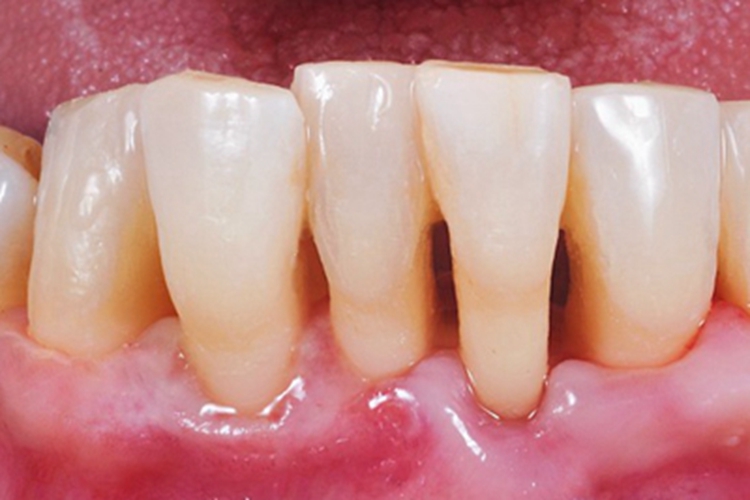

牙龈退缩可表现为下排牙龈萎缩,接近牙根处牙龈略显苍白,接近牙槽骨处的牙龈泛红肿胀,且牙根暴露,牙体变长,容易出现根面龋。

牙龈退缩可能是由于不当的刷牙技术、牙周病菌的侵袭等因素引起的。牙周病菌会产生毒素和酶,导致牙周组织的破坏。牙龈退缩后,牙颈部分暴露,容易积聚菌斑,继续刺激牙周组织。长期刺激和感染,便会导致下排牙龈萎缩红肿。